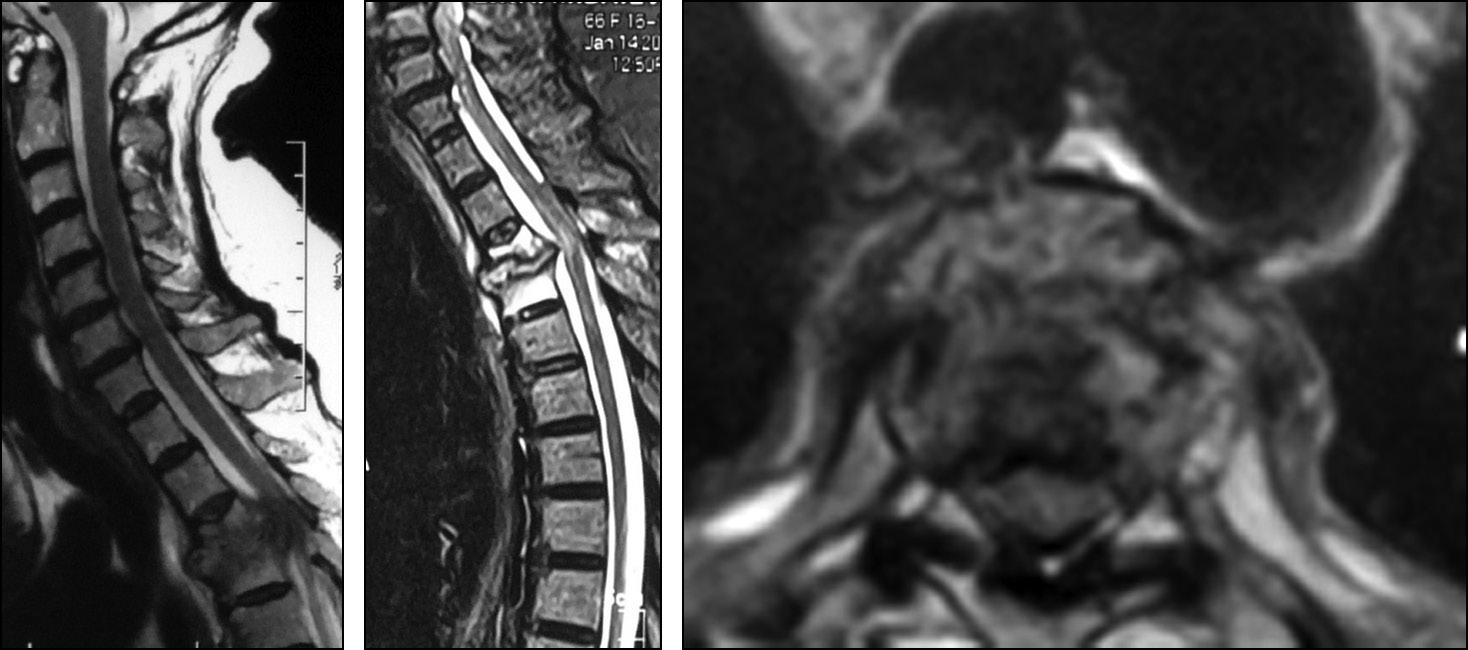

На МРТ грудного отдела позвоночника выявлен спондилодисцит Th3-Th4 с патологическим переломом тела Th3 и кифотической деформацией и сдавлением спинного мозга, эпидурит на уровне Th3-Th4 (рис. 3).

Рис. 3. Результаты выполненных магнитно-резонансных томографий грудного отдела позвоночника.

Fig. 3. Magnetic resonance imaging results of of the thoracic spine.

Клинико-рентгенологическая картина, данные МРТ и наличие в анамнезе ревматоидного полиартрита с поражением тазобедренных суставов позволили предположить воспалительную природу заболевания или, точнее, последствия этого. Поскольку клинически и рентгенологически у больной имелось переднее сдавление спинного мозга, была показана операция — передняя декомпрессия, передний спондилодез и металлофиксация.